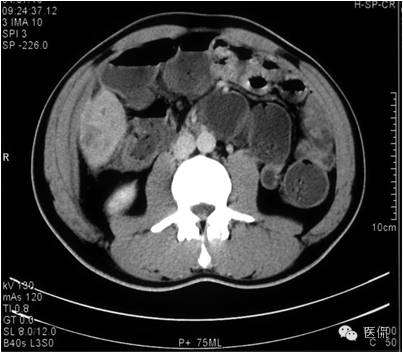

延迟期密度略有下降,但仍有强化,形态不规则。

手术病理诊断:

肝炎性假瘤,侵及周围结肠和腹壁,浸润组织有水肿,粘连。